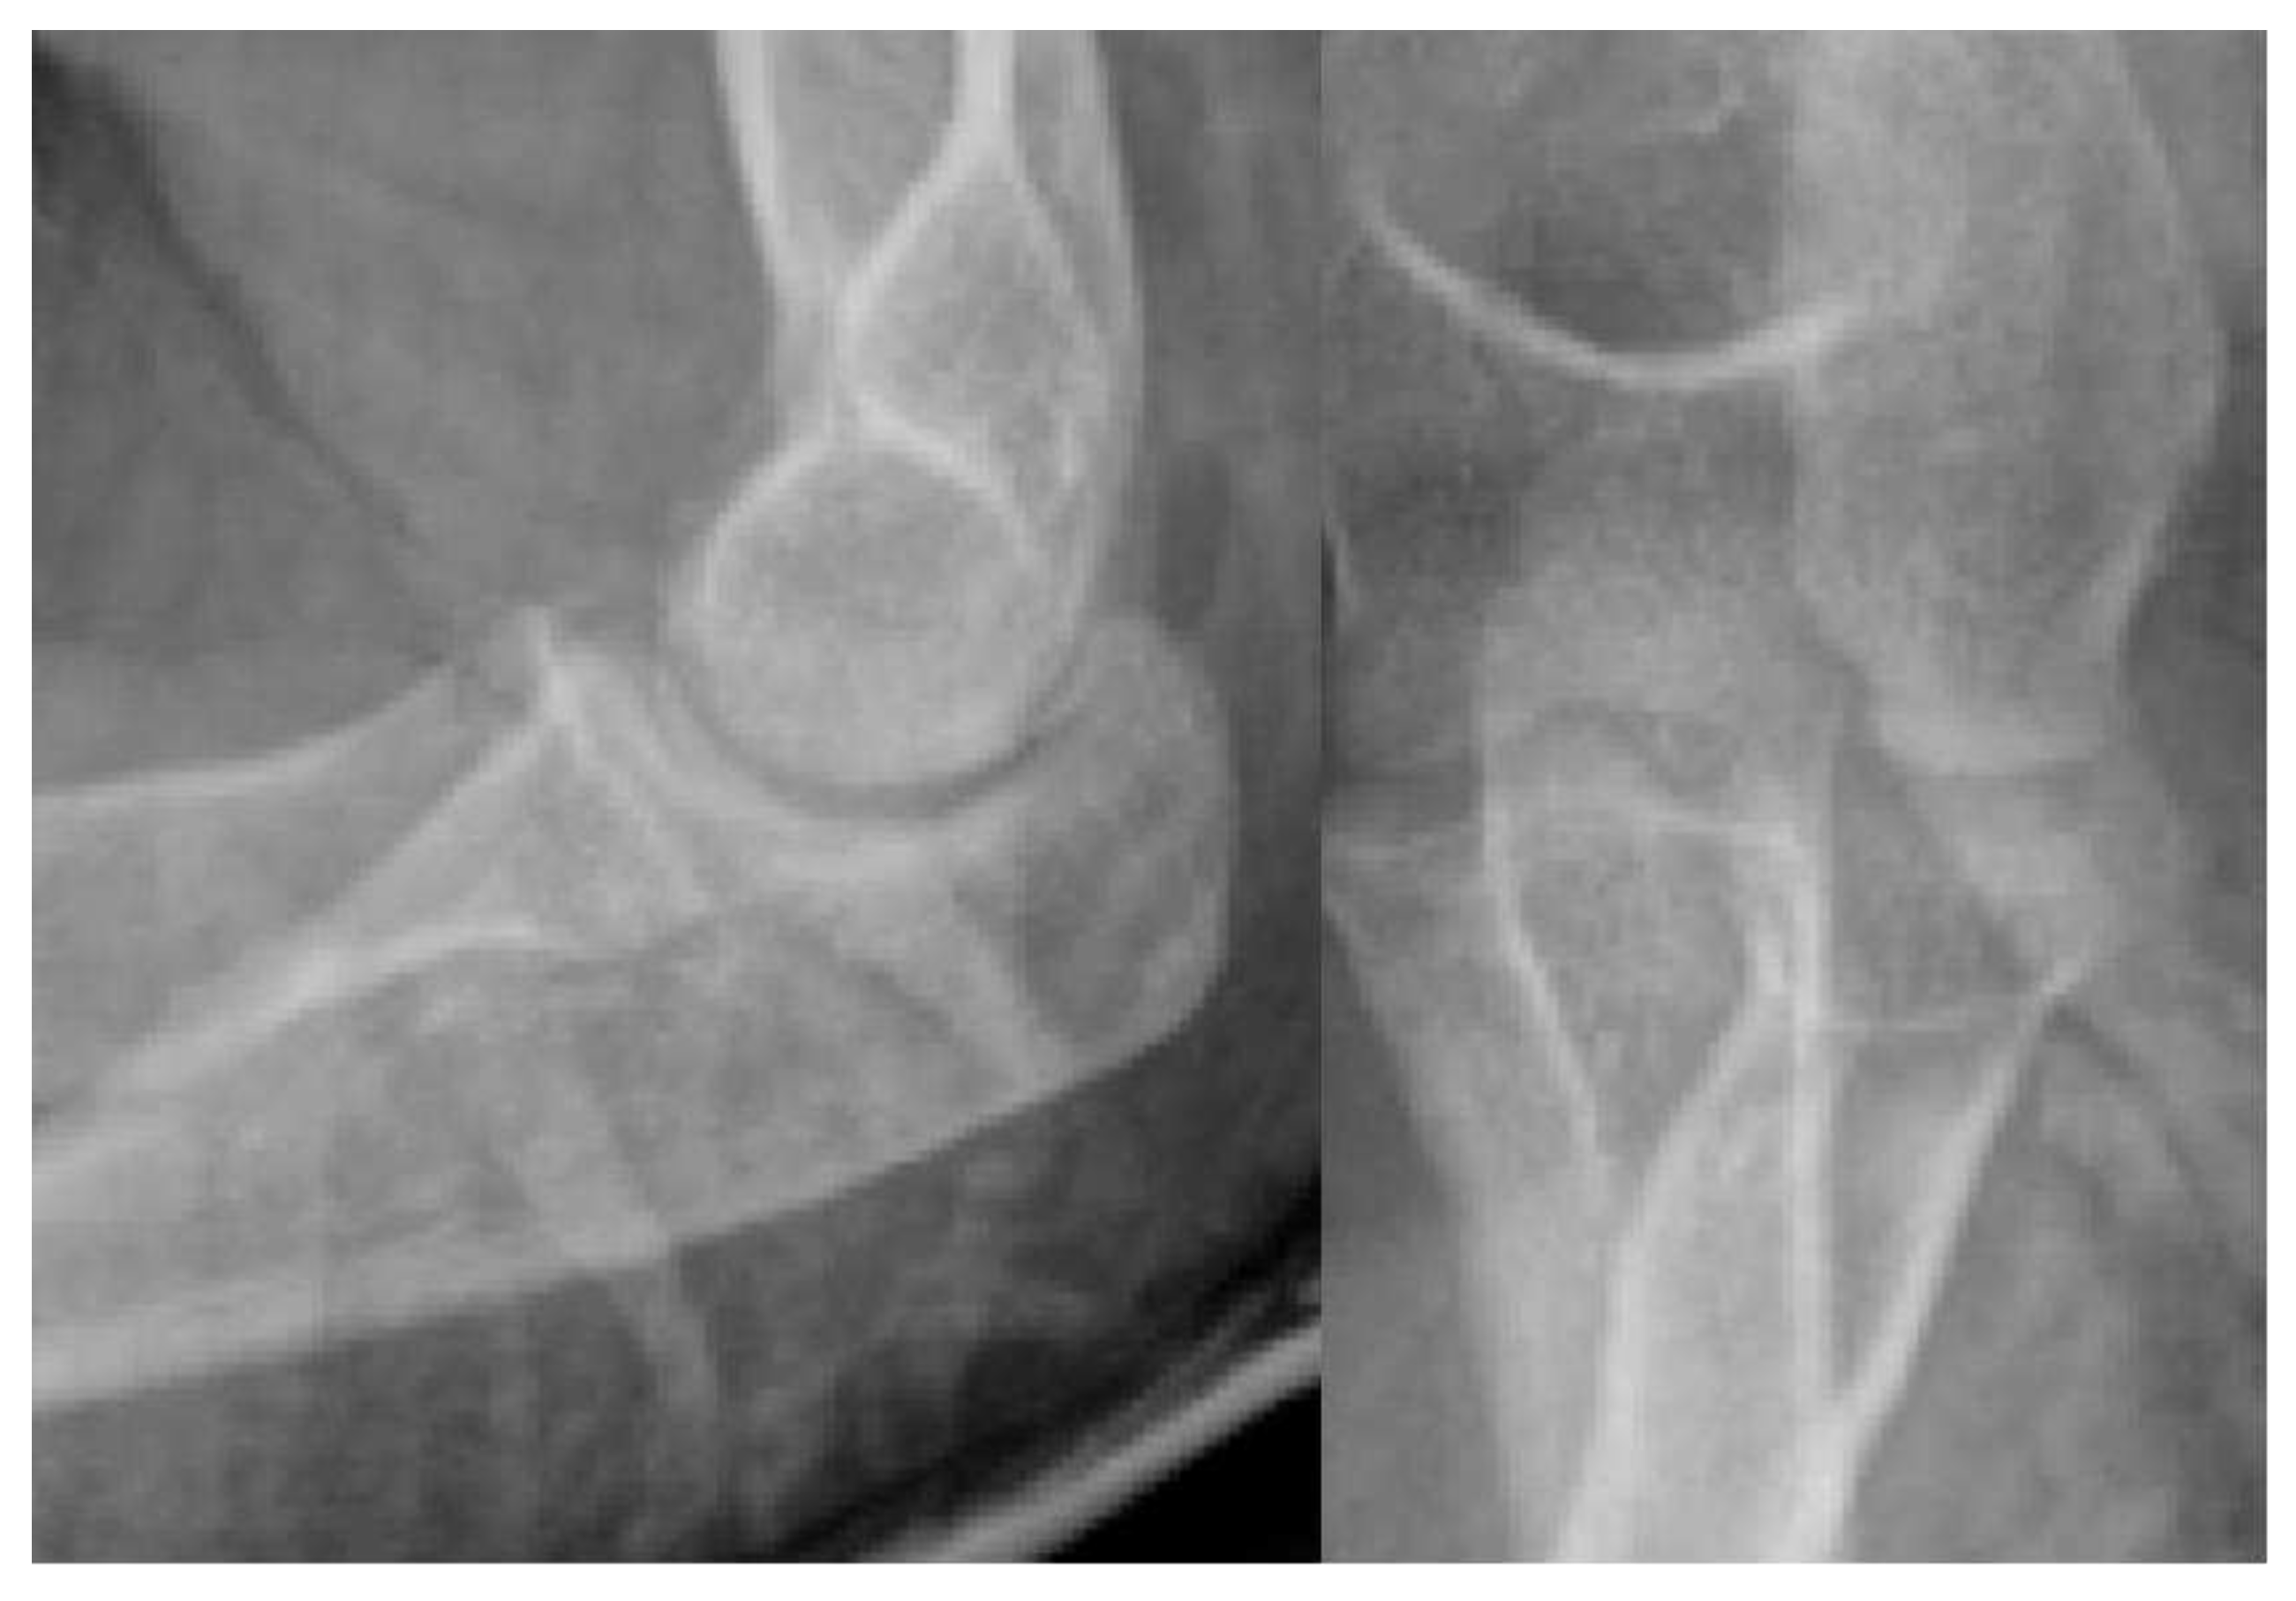

- X-ray: Lucency between fragment and normal bone.

- X-ray: Loose body, lucency

- X-ray: Secondary Osteoarthritis